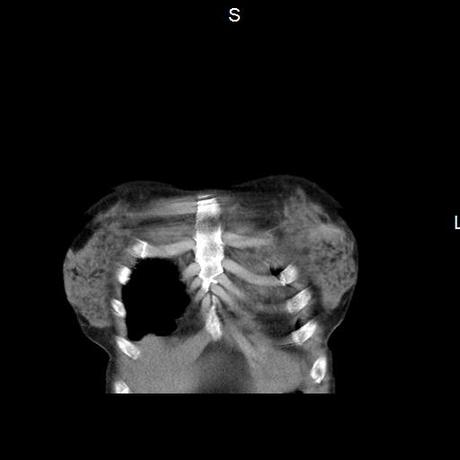

Se realiza volumen de tórax en fase simple, desde los opérculos torácicos hasta los hemidiafragmas, observándose:

El parénquima pulmonar con areas parcheadas difusas en vidrio despulido combinadas con otras areas hipodensas de baja atenuación debidas a atrapamiento aéreo y engrosamiento intersticial y zonas de fibrosis de predominio en lóbulos medios e inferiores de ambos pulmones.

- LOS HALLAZGOS PUEDEN ESTAR EN RELACIÓN A NEUMOPATIA INTERSTICIAL PROBABLE ETIOLOGIA HIPERSENSITIVA VS AUTOINMUNE/BACTERIANA/FUNGICA.